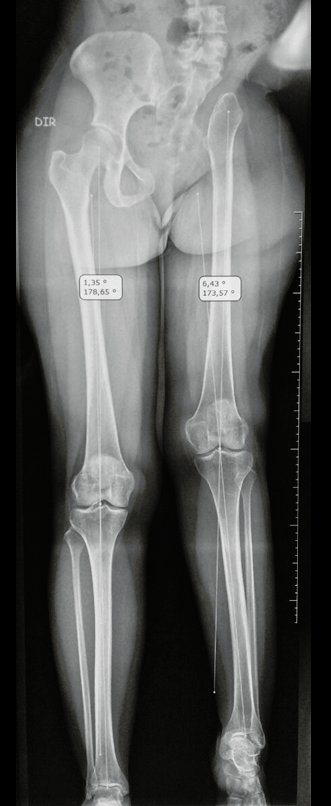

La paciente muestra felizmente su vida sin limitaciones importantes. Muestra superación completa del déficit funcional, realizando con soltura las actividades de la vida diaria, figuras 81 a 90.

Vídeo 1 : Marcha con apoyo total en la extremidad operada, carga en una sola pierna con buen equilibrio, buena función de flexión de caderas y rodillas con carga. Excelente resultado funcional de una hemipelvectomía interna total, sin reconstrucción, a 12 años y tres meses de la cirugía.